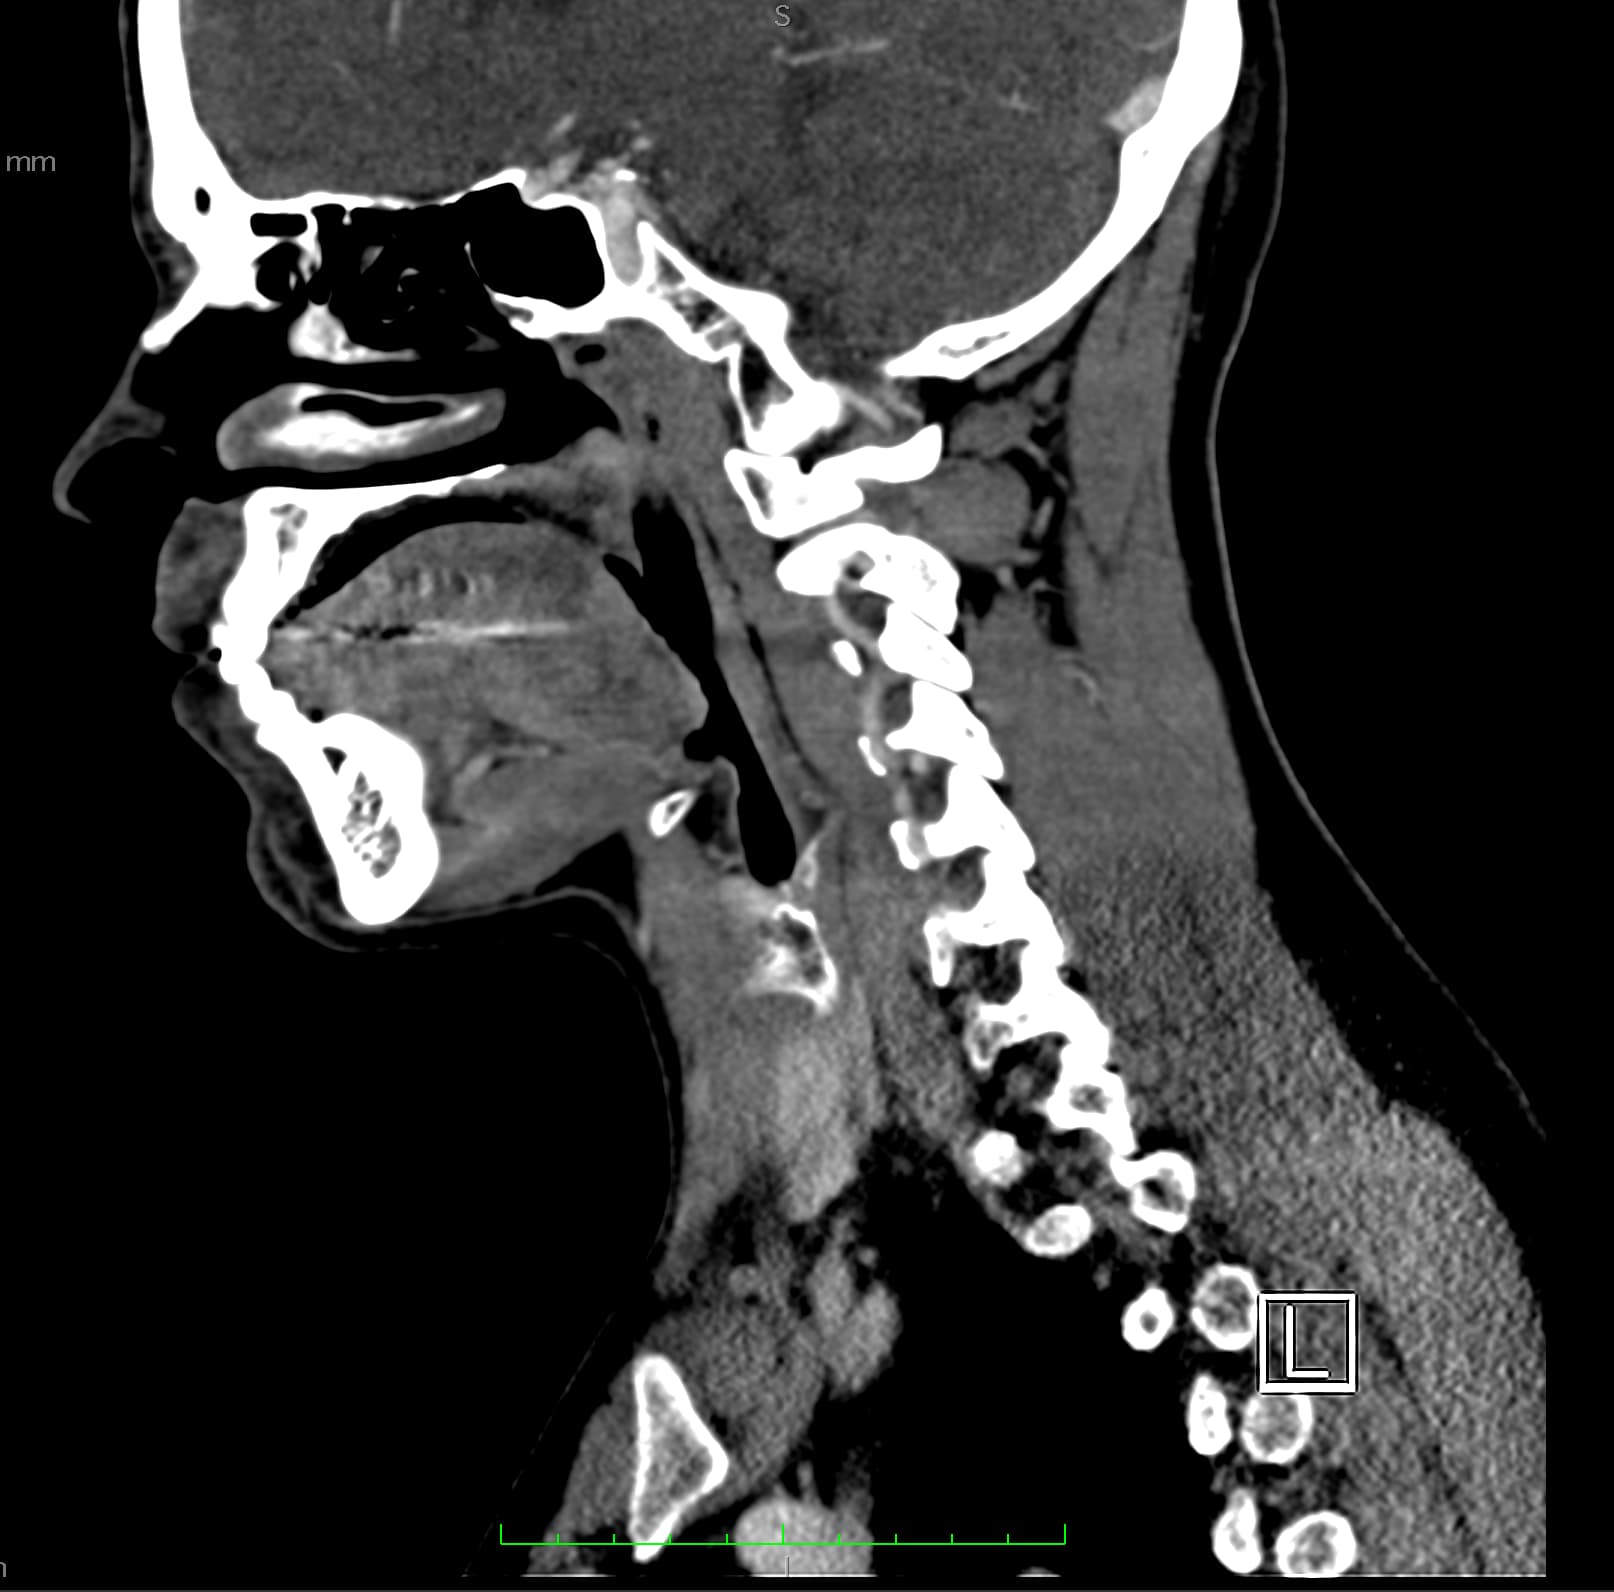

So, 2 years ago was the first time I came across Living with Eagle, filled with descriptions of all my symptoms, and a slew of scans showing very obvious bone chunks in the neck. Since I studied bio in college, and these bones are obvious, I figured I’d take a stab at looking at my own past scans and, low and behold, mild–but present–ossification of my stylohyoid ligament. Perhaps more relevant in my case, in the process of learning enough of the anatomy to understand axial images I noticed another weird thing–my right external carotid artery is in the wrong place. Instead of sitting lateral to my hyoid greater cornu, it’s medial. Hmm.

Tonsil surgery did solve the problem of my tonsils hurting, because they were gone, but no resolution of other symptoms. This was a year ago. I’ve been to PT, SLP, and now back to PT while I trial gabapentin for the neurologist. PT#2 discovered a bunch of significant atrophy in my upper right shoulder/back, and, you guessed it it’s all right sided. I’ve since then, thanks to radiopedia and Netter’s, also explored my images and noticed a few other anomalies in my scans, including an extended right thyroid superior cornu which appears to be pressing strongly into my neck also in the general area of pain, and an occipital artery branching off and wrapping around the internal carotid. Frustratingly these also weren’t mentioned on rads reports. My swallow study by the SLP showed obvious asymmetry with my swallow, but the SLP reported it symmetric and radiology apparently doesnt read the A/P view in their modified barium swallow studies? This is not inspiring faith in the academic institution I attended, but what can I possibly know they dont?

I’m here cause I’ve learned so much, and ya’ll seem to be the internet experts of weird head/neck issues adjacent to the stylohyoid chain. The docs keep seeing me, and keep ordering imaging, and seem to not be talking to each other at all? Frankly it seems to me the answers are in already in the images… so I’ve included several, perhaps you’ll see something helpful and can offer a suggestion… I just know I’m exhausted, frustrated, in so much pain all the time I cannot function which is so demoralizing, and it’s getting worse despite physician recommendations.

I wish I had better words for my existing doctors, or a doctor to visit familiar with these symptoms, if they’re sufficiently connected. Here are some scans for those interested, maybe someone has some ideas I can share with one of my doctors. I’m definitely at a loss and the pain constant and debilitating.